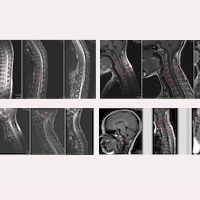

小腦扁桃體下疝第一型/Chiari畸形第一型

脊髓空洞症